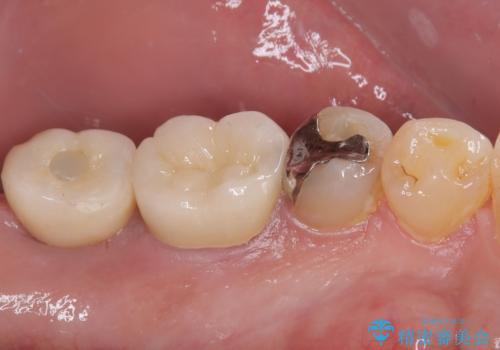

- 食事などで噛んだ時に奥歯が痛むとのことで来院された患者様です。

レントゲン写真より、一番奥の歯の根尖部に大きな病変(炎症により骨が溶けている状態)が認められたため、根管治療を行うこととしました。

インプラント治療まで待機している間に、手前のむし歯処置されている歯が強い痛みに襲われ、確認したところ、既に神経組織が壊死している状態であったため、根管治療を行い、インプラント部と合わせて補綴治療を行いました。